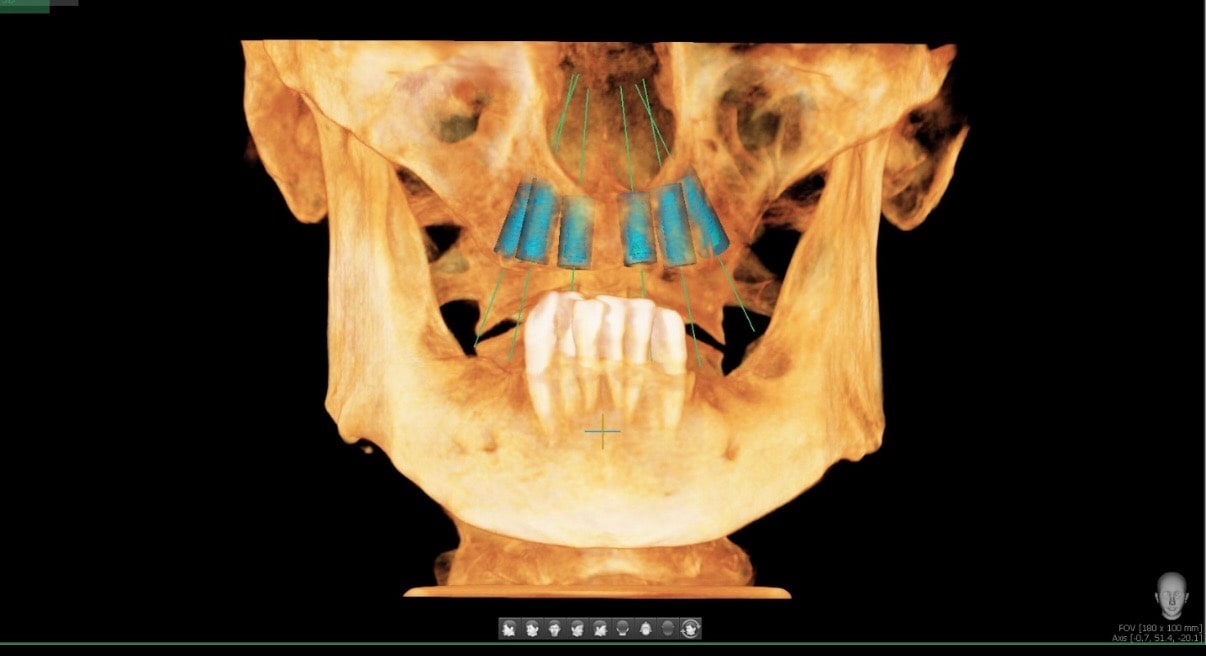

We knew that John was a good candidate for All-on-4 implants, so our team worked to design a bright, healthy smile for John. During our comprehensive examination, we took x-rays, surveyed the damage, and created an upper arch that restored the natural appearance of his teeth.